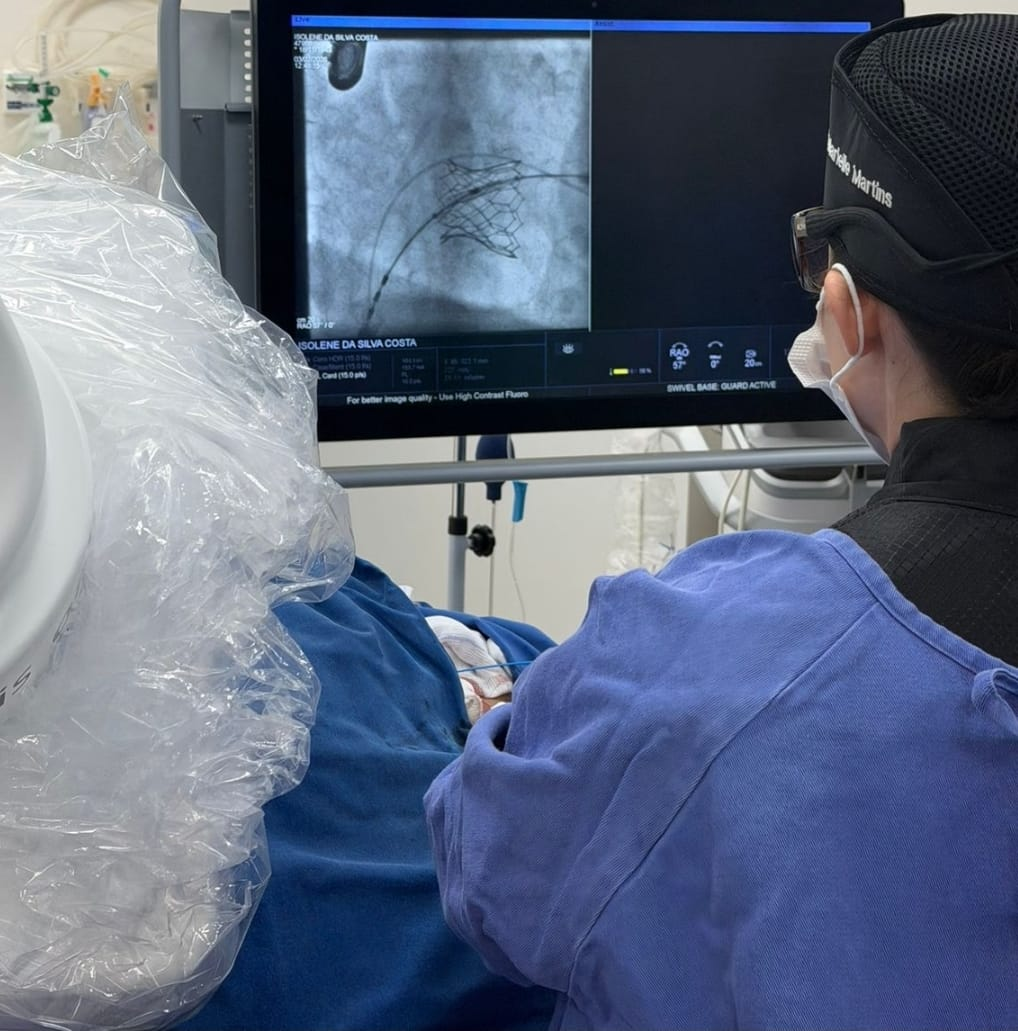

O procedimento é realizado em sala de hemodinâmica, com o implante de uma nova prótese por meio de cateteres guiados por exames de imagem, sem a necessidade de cirurgia aberta ou abertura do tórax.

A nova válvula é implantada por acesso percutâneo, geralmente pela veia femoral, e posicionada com auxílio de raio-X e ecocardiografia, podendo utilizar estruturas previamente existentes, como próteses antigas ou anéis de anuloplastia, para garantir a fixação adequada.